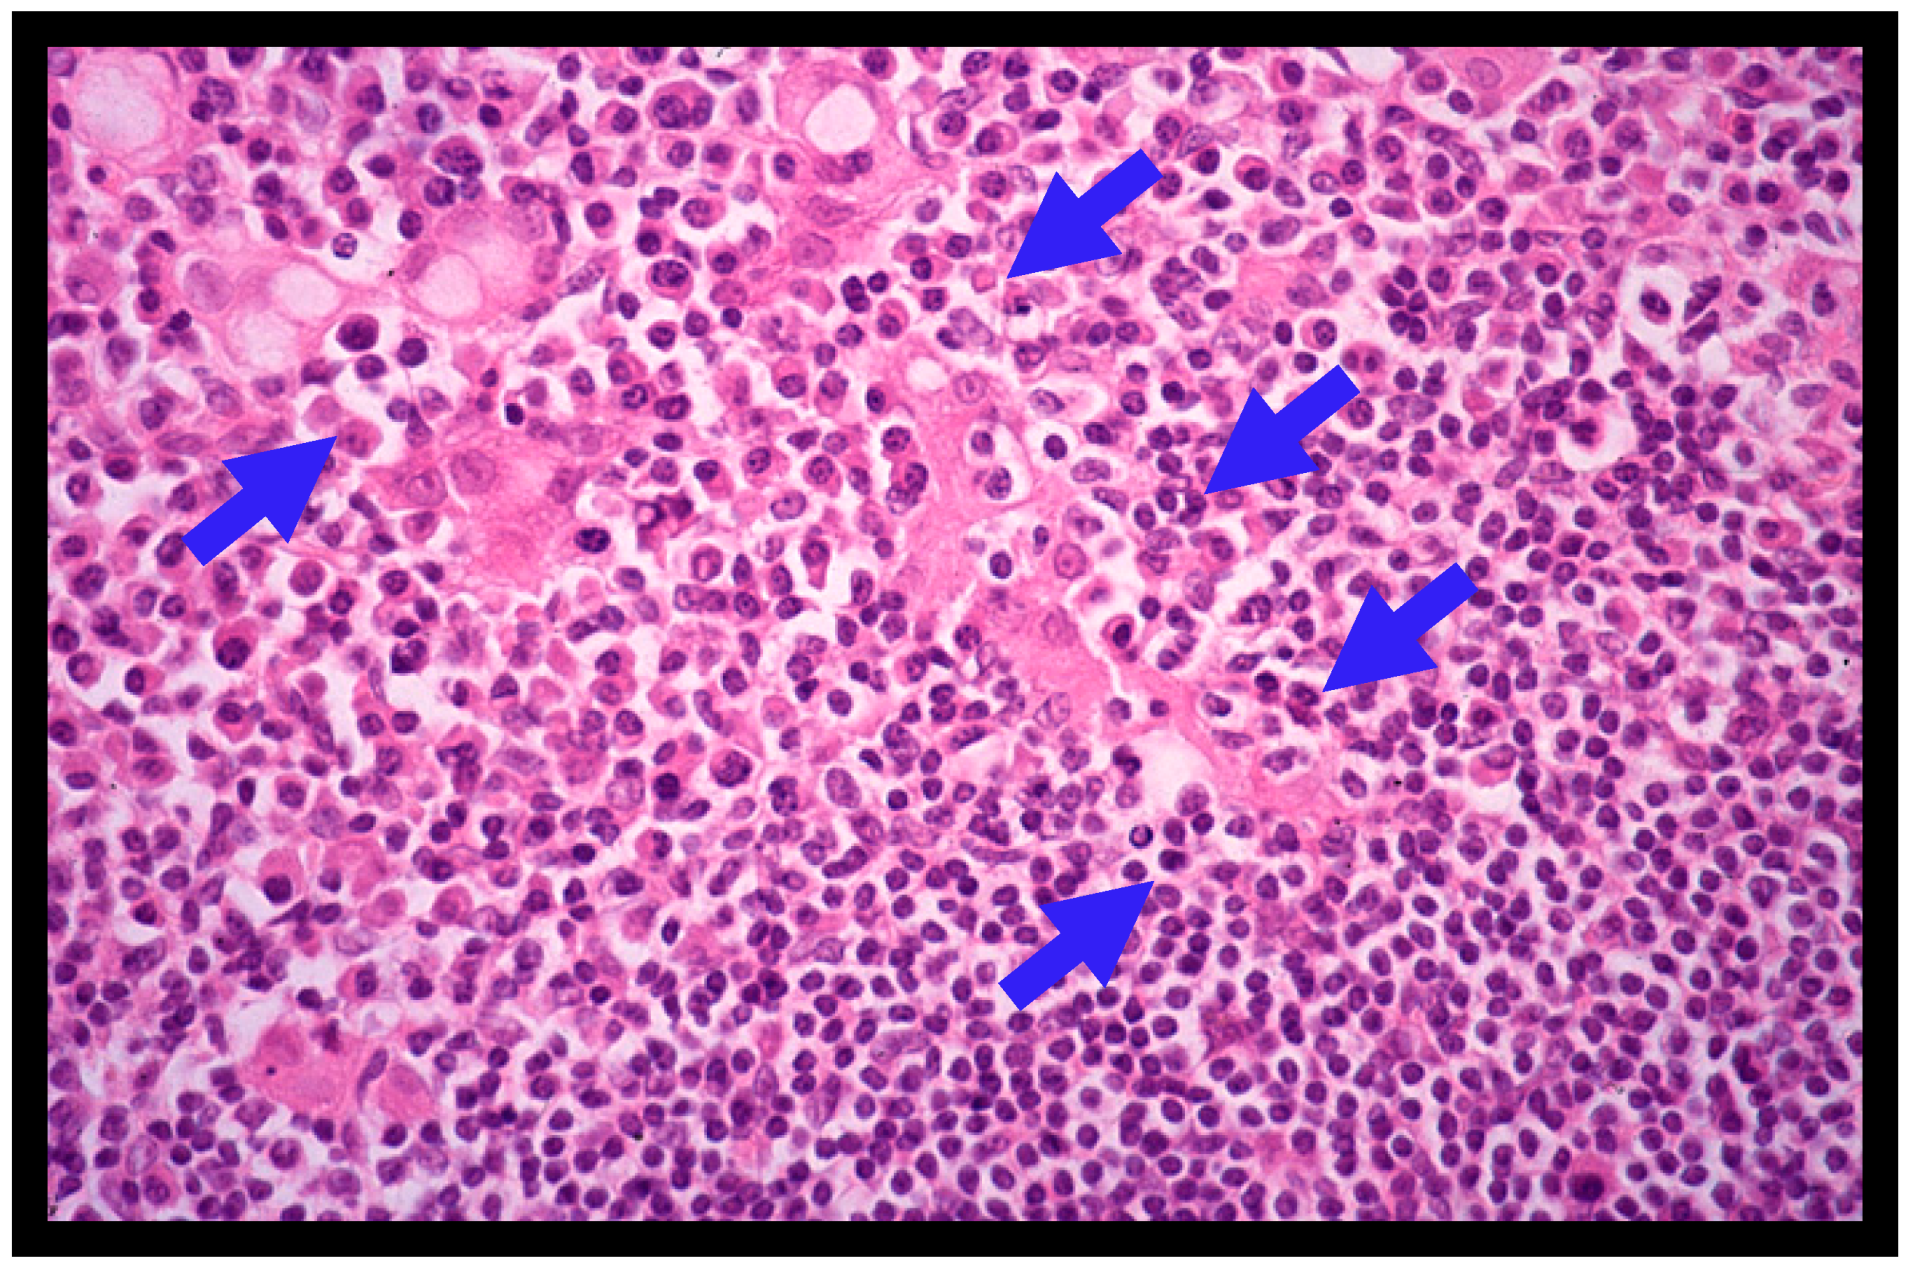

A definite diagnosis of gastric MALT lymphoma is made based on the histopathologic criteria of the World Health Organization (WHO) classification system [2,3], the Consensus report of the European Gastro-Intestinal Lymphoma Study (EGILS) group [29], and the National Comprehensive Cancer Network (NCCN) guidelines [30]. Histologically, the diffuse infiltrate of atypical neoplastic lymphoid cells (centrocyte-like cells) around reactive follicles showing a marginal-zone growth pattern, which often infiltrate into gastric glands causing the destruction of epithelial cells (lymphoepithelial lesions (LELs), Figure 2), is observed in gastric MALT lymphomas [1,2,3,4]. MALT lymphoma cells immunohistochemically exhibit CD20+, CD79a+, CD5-, CD10-, CD23-, CD43+/-, and cyclin D1-. However, when large lymphoma cells are present in a solid or sheet pattern, a diagnosis of DLBCL should be made [6,7,10,11]. DLBCL usually shows high Ki-67 expression upon immunohistochemical staining [6,19,20]. The histologic diagnosis of gastric lymphomas should be confirmed by an expert hematopathologist [1,2,3].

Figure 2.

Histological features of gastric MALT lymphoma (H&E; X400). Diffuse infiltrate of small- to medium-sized atypical neoplastic lymphoid cells (centrocyte-like cells) around reactive follicles with a marginal zone growth pattern is shown. Lymphoepithelial lesions (LELs) (blue arrows) are also shown.